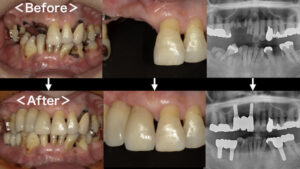

インプラントとは、顎の骨にチタン製のインプラント(人工歯根)を植立し、それを土台に上から人工歯を被せることで、歯の欠損を補う治療方法のことです。当クリニックではオペ専用の診療室を完備し、インプラント治療に力を入れております。おかげさまで数多くの治療実績を確立し、他の歯科医院様からの委託を受けてのインプラント治療も行っております。

抜歯即時埋入

これまでのインプラント治療では最低でも2回の外科処置が必要で、治療期間が長期にわたるため患者様の負担が大きくなるデメリットがありました。抜歯即時埋入は治療期間を短くできるので、患者様の時間的・費用的負担を軽減できる治療法です。